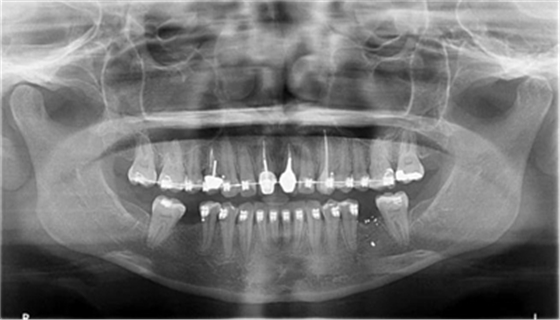

圖1a.病例1在正畸排齊后的臨床和放射學(xué)檢查。曲面斷層片顯示初期治療后良好的牙根排列,但下頜右側(cè)第二磨牙仍舊有些近中傾斜

圖1b.臨床檢查顯示牙槽嵴萎縮,右下第一磨牙的無(wú)牙間隙近遠(yuǎn)中距離為6.5mm,左下第一磨牙為9mm

一位29歲的女性患者,雙側(cè)下頜第一磨牙缺失,來(lái)院要求修復(fù)治療。缺失牙從未進(jìn)行修復(fù),導(dǎo)致牙槽嵴萎縮,第二磨牙近中傾斜,第三磨牙已拔除。其咬合關(guān)系為尖牙關(guān)系安氏II類(lèi)錯(cuò)畸形,作者團(tuán)隊(duì)決定通過(guò)正畸治療來(lái)糾正錯(cuò)畸形和改進(jìn)咬合關(guān)系。因此,其治療計(jì)劃包括雙側(cè)下頜第二磨牙直立和種植體支持式修復(fù)體來(lái)替代缺失的第一磨牙。

為患者采用了直絲弓自鎖托槽(Damon,Ormco)。最開(kāi)始用0.016×0.025 英寸的不銹鋼弓絲(Damon,Ormco)進(jìn)行矯正和排齊,歷時(shí)7 個(gè)月。在磨牙直立加力之前,下頜第一磨牙位點(diǎn)無(wú)牙區(qū)的近遠(yuǎn)中距離為右側(cè)6.5mm、左側(cè)9mm(圖1)。磨牙遠(yuǎn)移和直立的目標(biāo)是實(shí)現(xiàn)雙側(cè)最終冠修復(fù)體的近遠(yuǎn)中直徑達(dá)到10mm。右側(cè)第一磨牙位點(diǎn)的大小差異比左側(cè)更大,牙槽嵴吸收更多,頰舌徑約4.5mm(圖2)。在詳細(xì)解釋同期牙槽嵴增量和加速磨牙直立程序后,患者選擇右側(cè)位點(diǎn)進(jìn)行種植治療。因此,為了加速該位點(diǎn)的空間建立,圍繞第二磨牙行選擇性去皮質(zhì)術(shù)和同期牙槽嵴增量術(shù)。